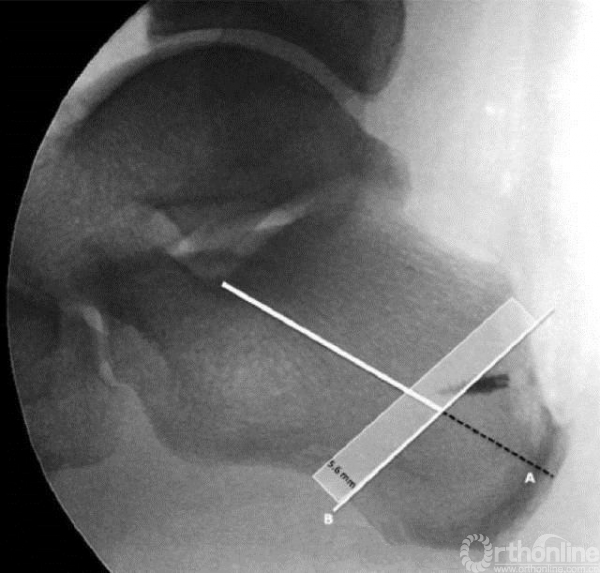

A线是自Gissane角向跟骨结节最后方划的一条线,

B线是平行于截骨方向的直线,它位于A线从Gissane角向远端走行的60%处。

安全区为B线近端5.6mm的区域内(图中阴影区)。